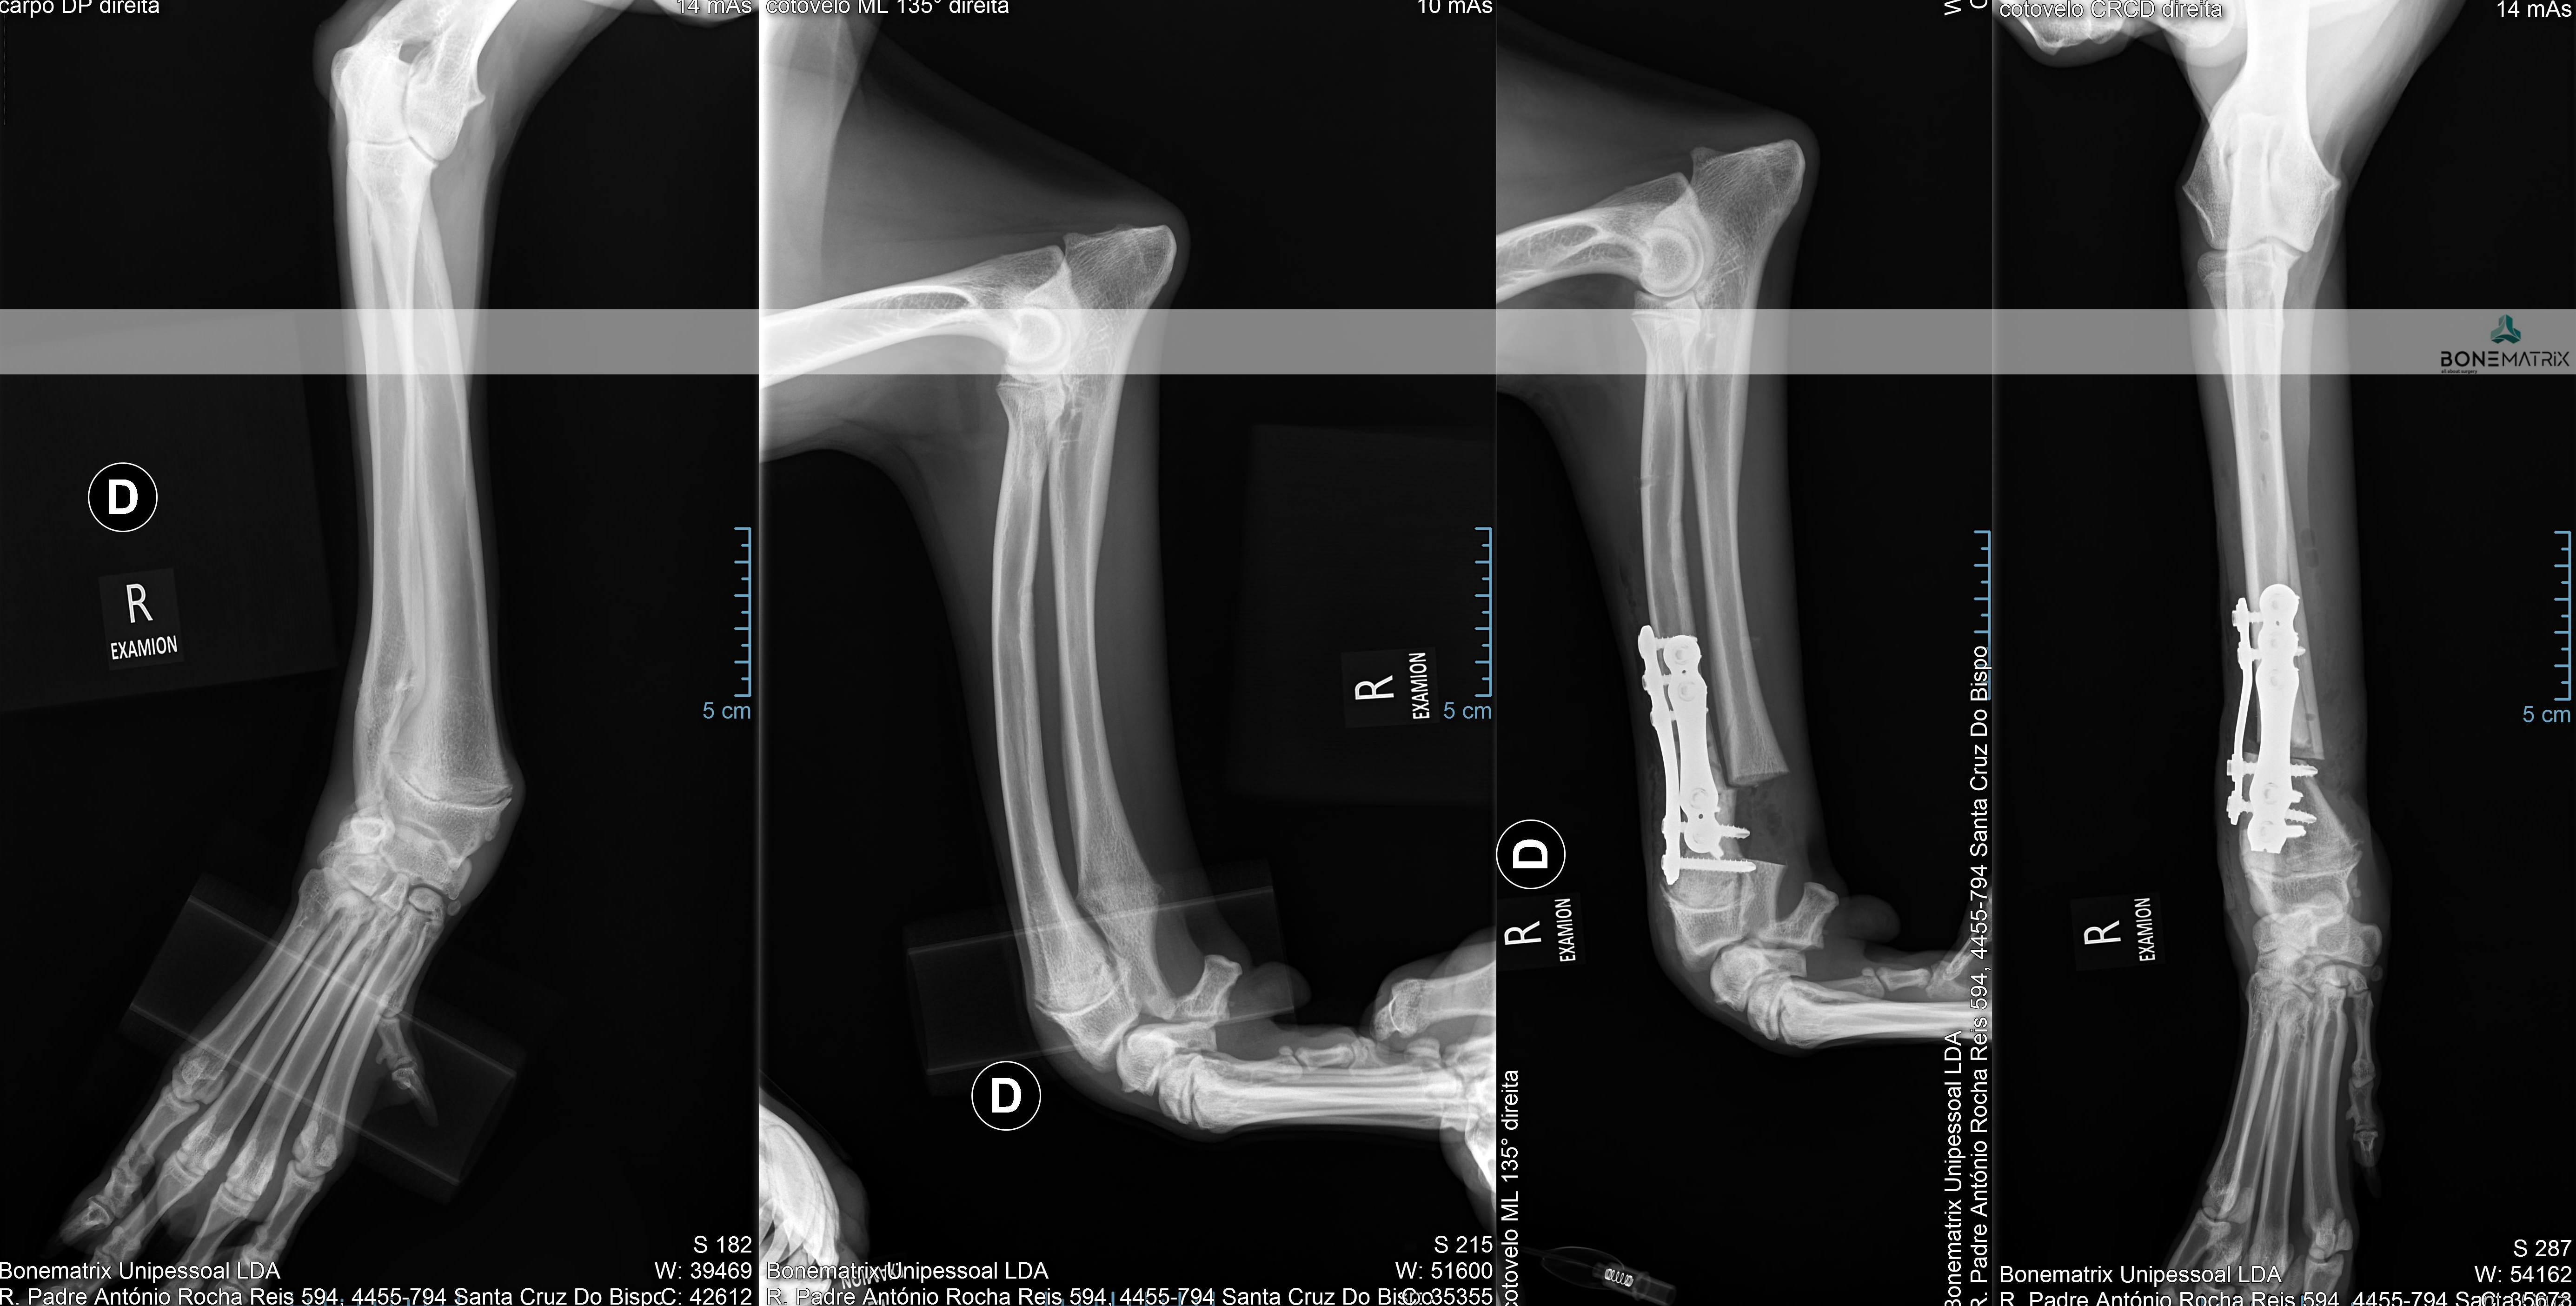

A displasia de cotovelo é uma doença de desenvolvimento caracterizada pela incongruência do cotovelo.

Dada a componente genética, frequentemente envolvida no decorrer deste processo, a patologia apresenta-se por norma bilateralmente, podendo assumir gravidade diferente em ambos os cotovelos.

Esta patologia quando unilateral, por norma, está relacionada com um evento traumático, ocorrido durante o crescimento do animal.

A displasia de cotovelo pode assumir várias apresentações, entre elas, a não união do processo ancóneo, a fragmentação do processo coronóide, a osteocondrite dissecante, doença do compartimento medial e a incongruência per si.

Todas estas apresentações tem em comum contribuírem para o desenvolvimento acelerado de um quadro de osteoartrite a nível intra-articular.

Como é criada esta incongruência?

A articulação do cotovelo é constituída por 3 ossos, o rádio, a ulna e o úmero.

A incongruência do rádio resulta na apresentação deste osso mais curto que a ulna. Isto resulta num excesso de pressão sobre regiões da ulna - resulta com frequência na fragmentação do processo coronóide.

Quando a apresentação contrária ocorre, ou seja, o rádio apresenta-se mais elevado que a ulna, é exercida demasiada pressão sobre o processo ancóneo - resultando com frequência na não união do processo ancóneo.

Quando a incongruência envolve o úmero outras lesões podem ser desenvolvidas que envolvem o desalinhamento articular entre o úmero e a ulna.

As incongruências descritas também podem ser consequência de um encerramento precoce traumático das placas de crescimento destes ossos (locais responsáveis pelo crescimento longitudinal dos ossos).

A apresentação desta patologia em fases iniciais apresenta, com frequência, sinais subtis, daí a necessidade de realização de despiste de displasia de anca durante o crescimento do animal (idealmente 5 meses) para que a doença possa ser detetada antes que ocorra um desenvolvimento significativo de lesões de osteoartrite a nível intra-articular.

O diagnóstico pode ser realizado por meio de estudo radiográfico.

Contudo são indicadas técnicas de imagem avançada (tomografia axial computorizada) ou artroscopia para a realização do diagnóstico final e definição de abordagem terapêutica.

O tratamento depende da forma de apresentação da doença a nível articular.

Vários são os procedimentos terapêuticos que podem ser feitos com recurso a artroscopia, nomeadamente desbridamento de lesões cartilagíneas, remoção de fragmentos do processo coronóide, remoção sub-total do processo coronóide, assim como também é possível a remoção de flaps de lesões de osteocondrite dissecante.

A resolução da incongruência articular é realizada por meio de um corte corretivo realizada na ulna. Este corte vai permitir que este osso se readapte à articulação de forma a que todas as estruturas constituintes da articulação suportem o peso de uma forma equilibrada, sem sobrecarregar nenhuma região. A cirurgia realizada com maior frequência neste sentido designa-se por PLUS.